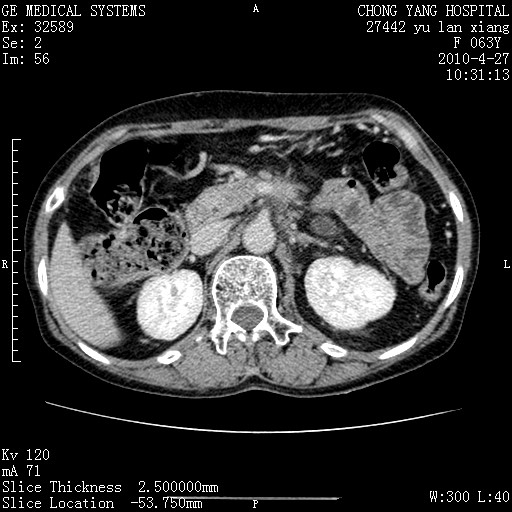

标题: CT26066:F63Y 上腹正中压痛半月,CA199:7400u/ml,MR示胰腺炎伴 [打印本页]

胰腺癌侵犯腹腔动脉干-分支、胃壁、左侧膈肌伴胰周及腹膜后淋巴结转移、胆囊切除术后。

胰腺癌侵犯腹腔动脉干-分支、胃壁、左侧膈肌伴胰周及腹膜后淋巴结转移、胆囊未显影。